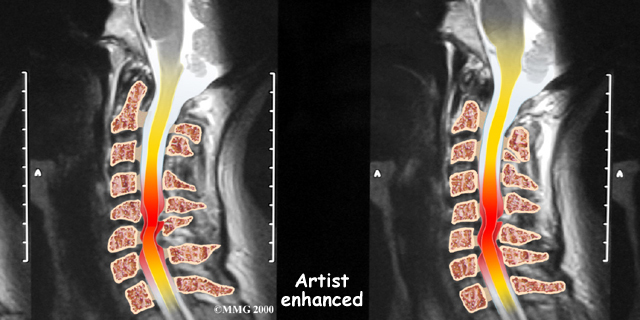

If more information is needed, a magnetic resonance imaging (MRI) scan may be ordered. The MRI machine uses magnetic waves rather than X-rays to show the soft tissues of the body. This test gives a clear picture of the spinal cord and can show where it is being squeezed. An MRI machine creates pictures that look like slices of the area your healthcare professional is interested in. This test does not require any special dye or a needle.